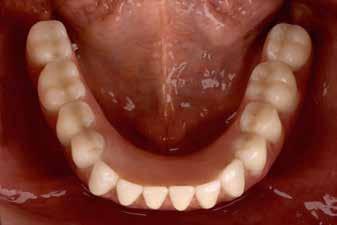

Interdiszciplináris fogászati kezelés myofunkcionális készülék, alignerek és protetikai ellátás alkalmazásával

MED. DENT Abradált frontfogakkal rendelkező felnőtt páciens interdiszciplináris kezelése